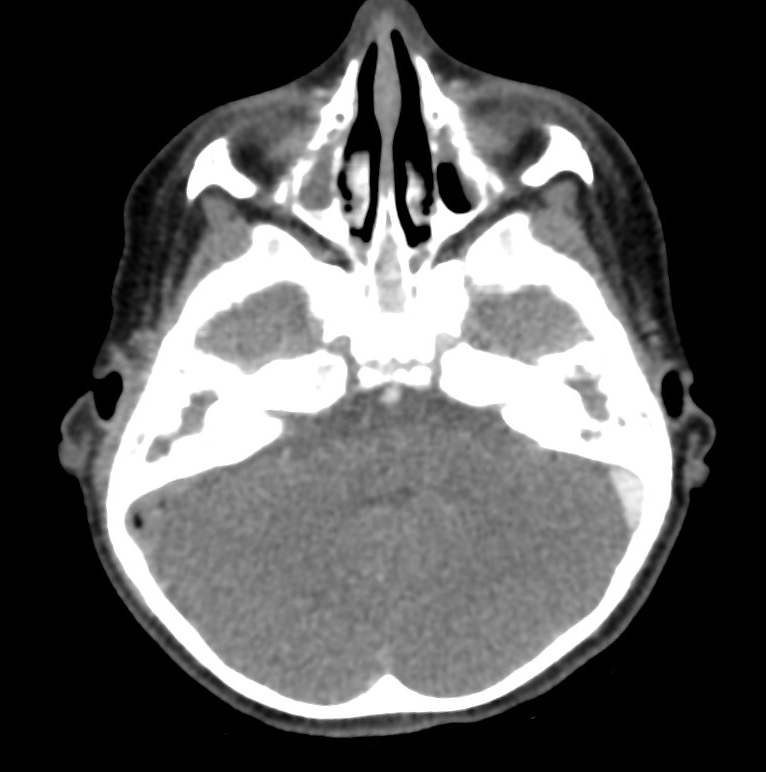

Voici l’imagerie que vous avez demandée. Devant le tableau, le radiologue a également choisi de faire une IRM.

Question 13 : Qu’en pensez-vous ?

Confirmée par la présence d’abcès sous-cutanés rétro-auriculaires droits (cf. question 4)

On voit bien une image plurilobée d’abcès à droite

On peut voir sur le scanner une image très hypodense dans le sinus à droite (alors que le sinus gauche est normalement hyperdense). C’est très visible sur la coupe en IRM avec un caillot hypo-intense au milieu du sinus veineux à droite

Comme expliqué à la question précédente, l’intérêt est de chercher les complications intracrâniennes. Il n’y a pas ici d’abcès intracrânien, mais on retrouve une thrombophlébite importante du sinus sigmoïde droit. Insérer image « Figure10.jpg ». Insérer image « Figure11.jpg ». Insérer image « Figure12.jpg »